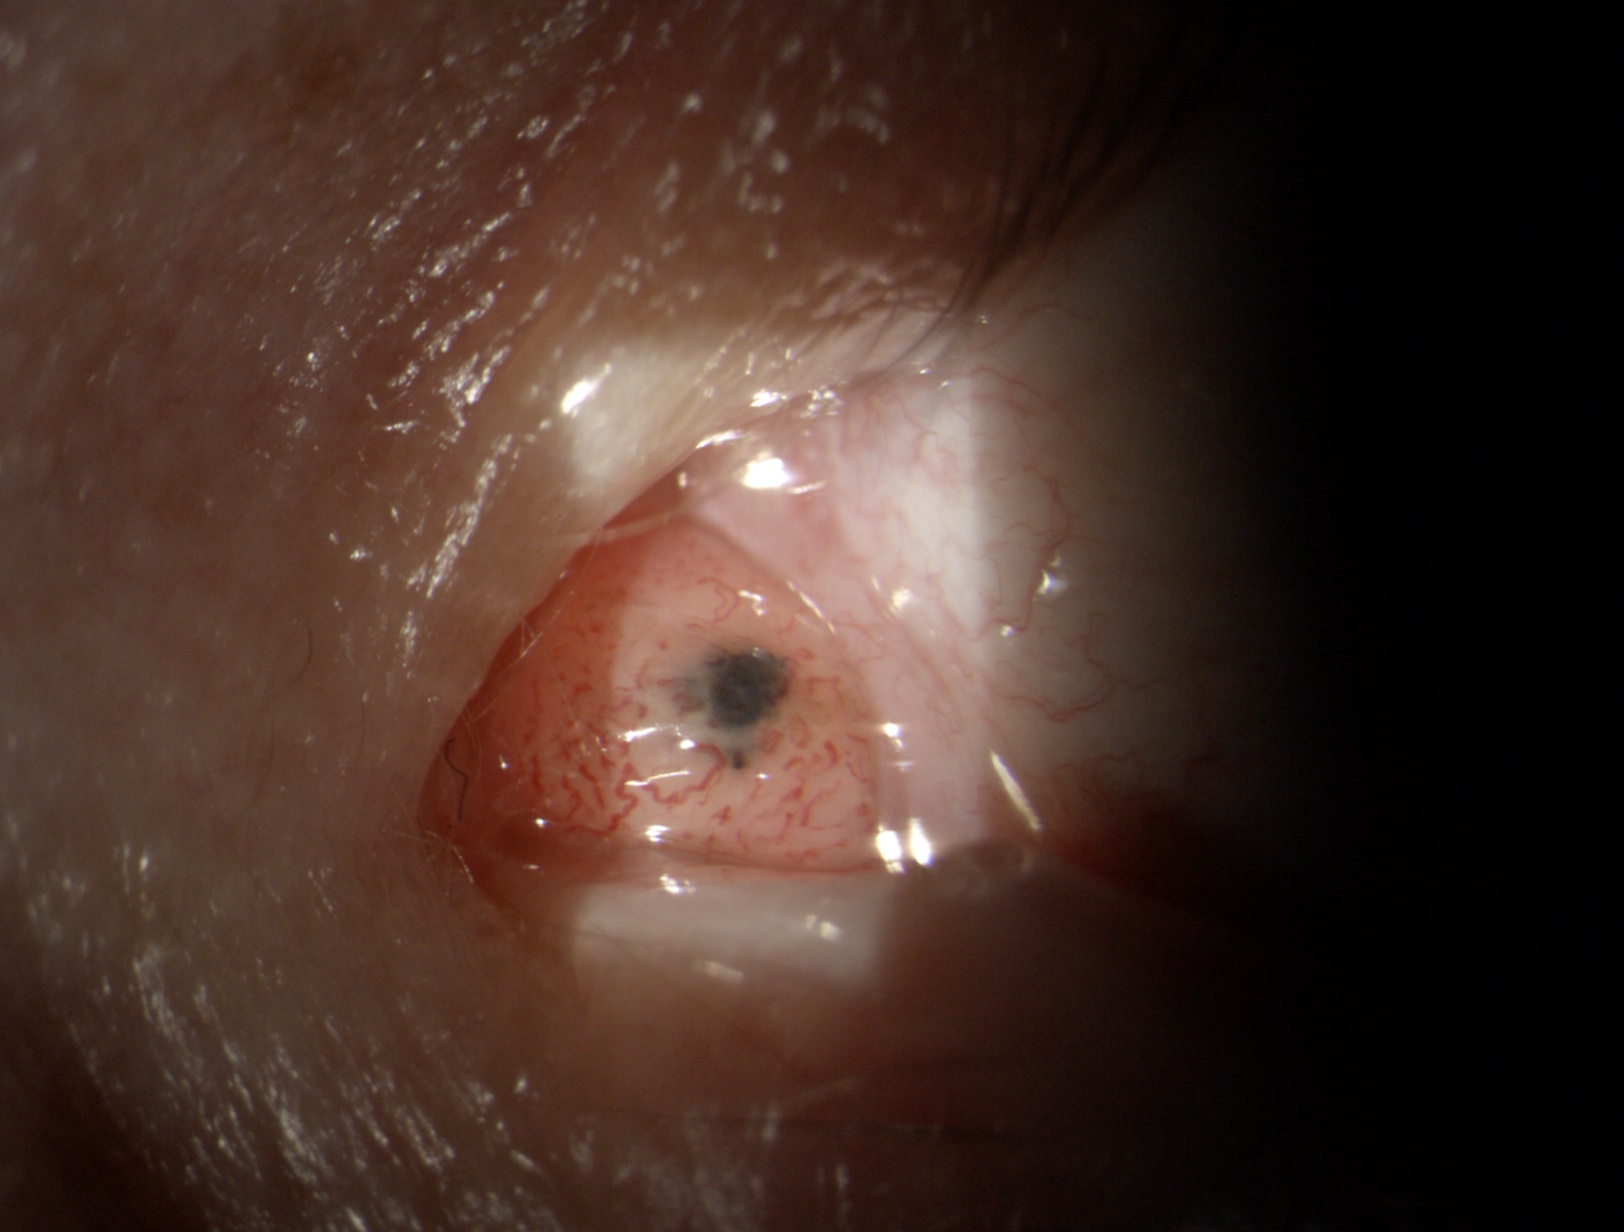

Abbildung 1: Charakteristische Rötung der Bindehaut bei mäßiger allergischer Konjunktivitis.

Abbildung 2: Typische Rötung der Bindehaut mit starker Zeichnung der Blutgefäße bei wiederholt auftretender allergischer Konjunktivitis.

Abbildung 3: Deutliche Schwellung der Bindehaut mit daraus folgender verminderter Gefäßzeichnung bei akuter allergischer Konjunktivitis.